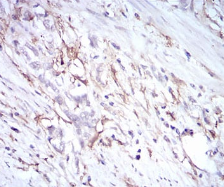

IHC    1/200 - 1/1000